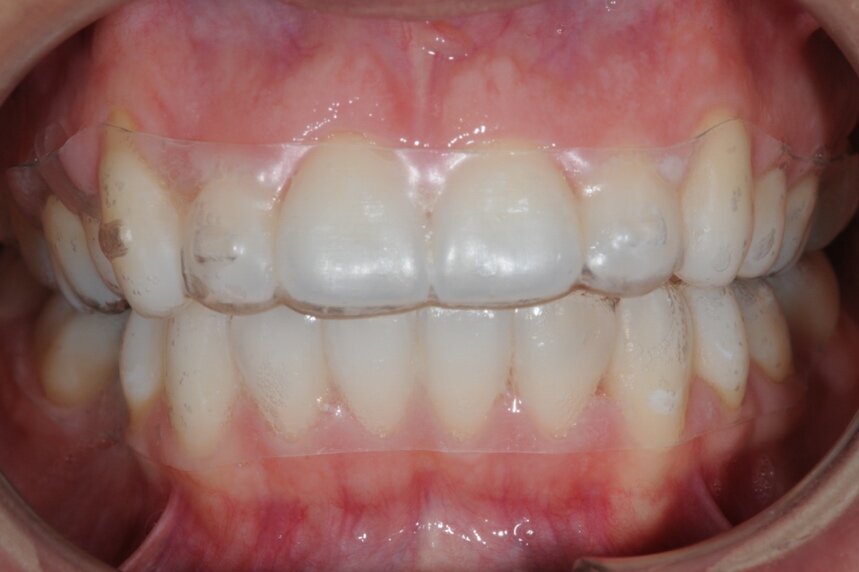

All’esame clinico del viso si osservava una sostanziale simmetria bilaterale e corrette proporzioni facciali verticali frontali e laterali (Figg. 1a-1c). Il sorriso presentava un’adeguata esposizione degli incisivi superiori e dei corridoi buccali e la centratura della linea mediana superiore rispetto al volto. All’ispezione del cavo orale, invece, si riscontrava una lieve deviazione della linea mediana inferiore verso destra di circa 1 mm, con contestuale II Classe canina a destra (Figg. 2a-2c). La mancanza del primo molare inferiore di destra aveva prodotto lo spostamento mesiale, la mesio-inclinazione del secondo e terzo molare inferiore e l’estrusione del primo molare superiore. A sinistra, invece, era riscontrabile una I Classe canina e molare. Erano presenti un moderato affollamento nell’arcata superiore ed un lieve disallineamento degli incisivi inferiori. L’overjet era lievemente aumentato e l’arcata superiore appariva lievemente contratta, soprattutto a destra. Erano presenti recessioni gengivali multiple.

Figg. 2a-2c - Foto intraorali pretrattamento: visioni frontale (a), laterali (b).